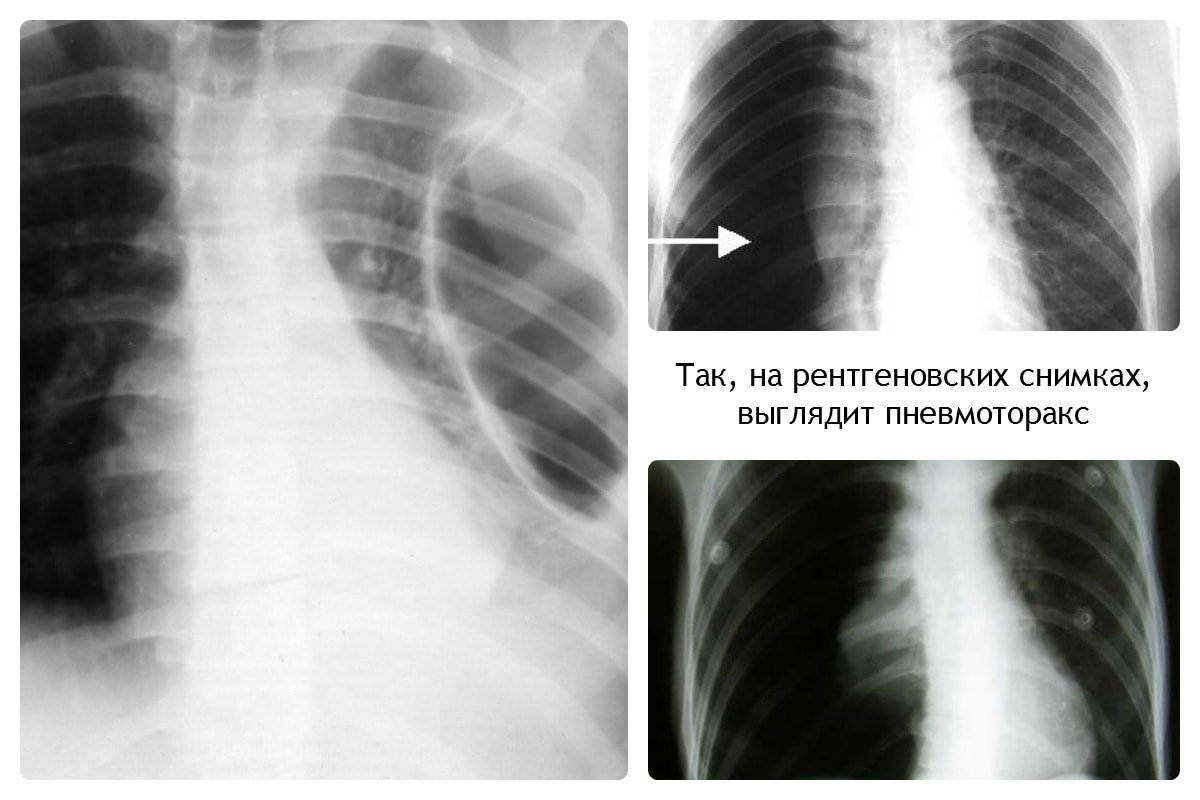

При пневмотораксе присутствует характерный уровень жидкости. На снимке отображается как просветление, лёгочный рисунок не просматривается.

Пневмоторакс

Важным этапом постановки диагноза остаётся отличие её от других заболеваний лёгких, коронавируса. Так, при бронхите будет отсутствовать затемнение на снимке, вместо этого — усиление лёгочного рисунка.

Усиление лёгочного рисунка

При плеврите, на снимке скопление экссудата в поражённой области. Плеврит выступает в качестве осложнения недолеченной пневмонии.

Плеврит